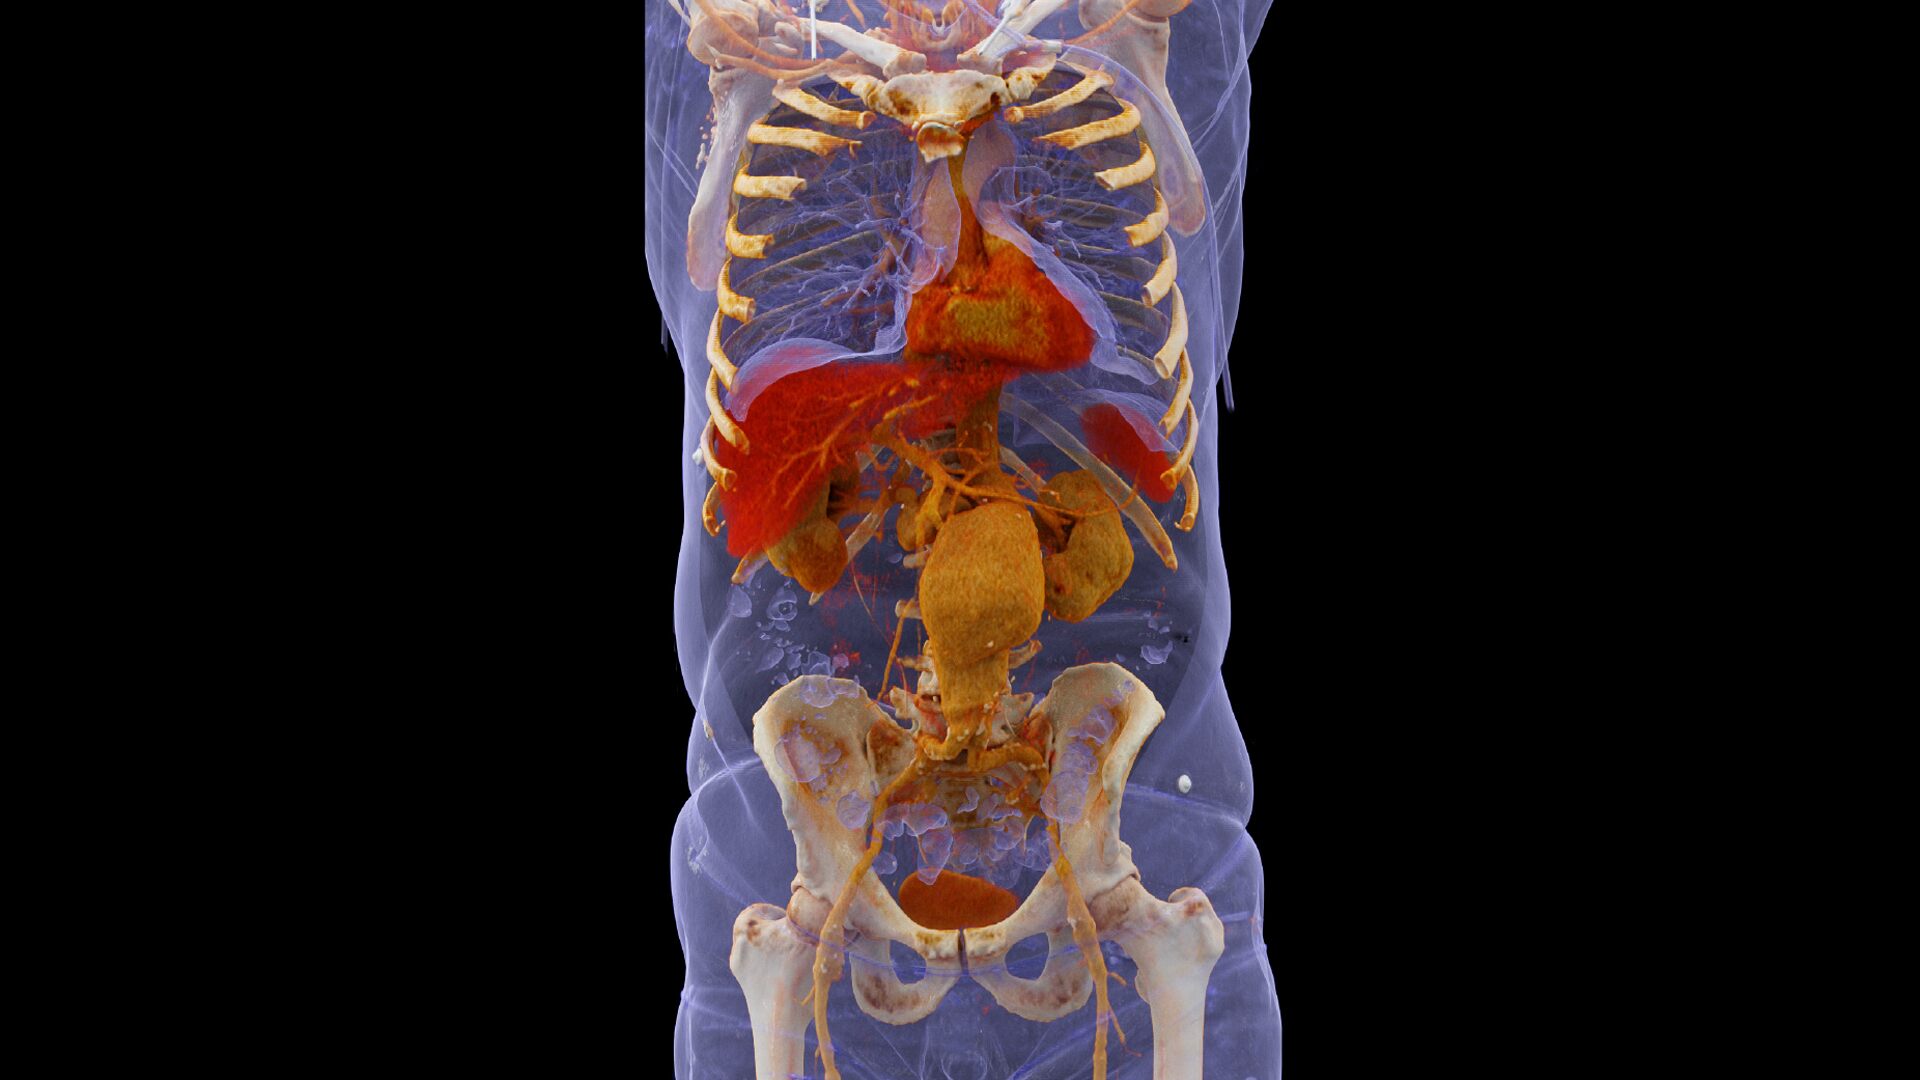

Несмотря на явные преимущества динамических исследований, применяемая в них доза излучения служит существенным препятствием для более широкого распространения этих методов, особенно для оценки перфузии внутренних органов. SOMATOM Force позволяет существенно снизить барьер лучевой нагрузки не только за счет расширения охвата до 22 см в перфузионных исследованиях (и до 80 см при КТА), но и путем снижения дозы облучения на величину до 50% по сравнению с тем уровнем, который характерен для ведущих КТ-систем. Теперь перфузионные исследования, например печени, можно проводить с дозой облучения сравнимой с дозой обычных многофазных исследований.

Исследования с низкой лучевой нагрузке без компромиссов качеству изображений - SOMATOM Force получает изображения с высокой скоростью и индивидуально подобранной дозой для каждого пациента, в том числе и в 4D.

Расширенная до 80 см динамическая КТ ангиография

Проводите функциональные исследования, такие как перфузия тела и динамическая КТ ангиография ультрадлинных диапазонов при низкой лучевой нагрузке.